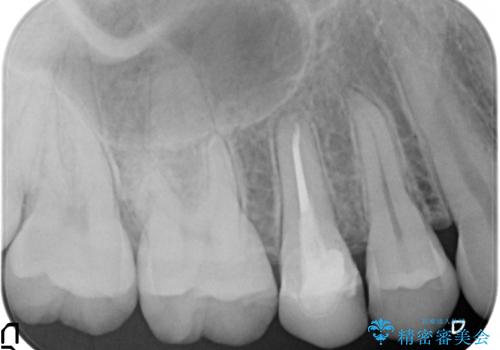

また、骨の高さを変えずに歯肉の奥深くまで削ると、歯肉の炎症になってしまいます。慢性的な炎症となり、すぐ出血するような状態が治らなくなってしまいます。

そうなると正確な歯型が取れなくなり、被せ物と歯の間に隙間が生じ、虫歯のリスクが飛躍的に高まります。歯肉の奥深くに隙間があるような状態は歯ブラシができないので悪化の一途をたどってしまいます。

奥歯の神経の治療および、土台は他院で行なっています。

角化歯肉の幅がしっかり合ったため、歯肉をずらすAPF(アピカリ)でなく、切除療法を行いました。

骨外科の量は多かったですが、術直後見られた動揺も治っています。